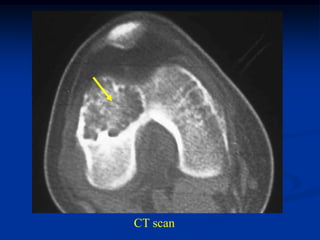

Case #637

12 year female with chondroblastoma prox femoral epiphysis

CT scan

Another CT cut

cartilage

giant cells

Photomic